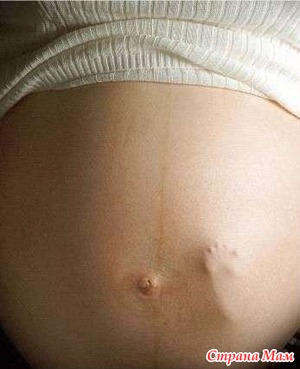

Добрый вечер!Ходила сегодня в больницу. Врач посмотрела и говорит, что если считать по месячным то у меня 39 недель, а вот УЗИ показывает 40-41 неделю. Говорит надо ложиться в больницу. И им спокойнее типа и мне. Решили что в среду с утра буду ложиться, а там видно будет.

Так что, родные мои, пожелайте мне, пожалуйста, удачи и легких родов. Вот так вот все 9 месяцев провела с Вами. Вы моя большая интернациональная семья. Всех Вас люблю!!!